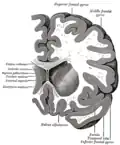

Transverse cut of brain (horizontal section), basal ganglia is blue